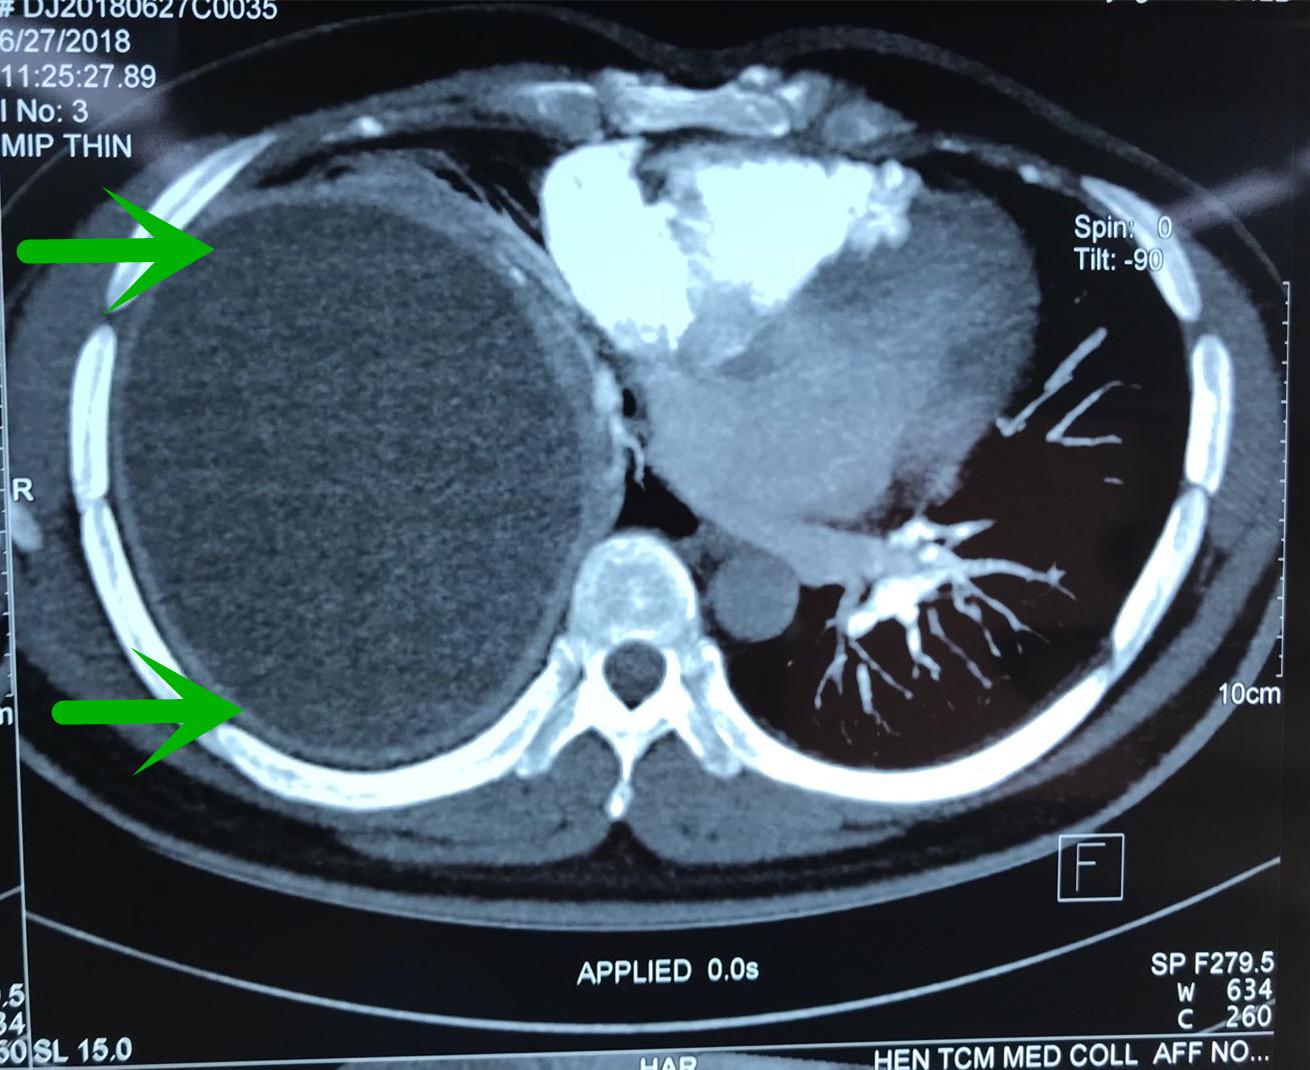

“拿到患者的检查结果,我们发现患者胸腔里长了一个足球大小的囊肿,已经快把右肺压瘪了,难怪他总是说胸闷、喘不过来气。”该院呼吸科王至婉教授说,患者胸腔内这个囊肿的体积有15×15×25cm那么大。由于囊肿的压迫,患者的右肺已经失去了呼吸功能,仅靠左肺来维持呼吸。

但这次李先生的情况不同寻常,由于右肺完全被挤压到肺门附近,加上右肺被压迫时间长,胸腔内囊肿巨大,可操作的空间极其狭小。同时囊肿和肺组织、主动脉、心包、膈肌、胸壁等周围重要组织粘连紧密,手术难度特别大,风险极高,手术中操作稍有不慎,就可能导致患者胸腔大血管破裂大出血,危及生命。